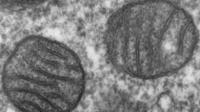

В крови пациентов с длительным COVID обнаружены аномальные микроструктуры

Ученые обнаружили скрытые физические изменения в организме, которые могут быть причиной длительного недомогания, испытываемого некоторыми людьми после перенесенного COVID-19. Анализируя образцы крови пациентов с длительным COVID, международная команда медицинских исследователей выявила необычные микроскопические структуры, способствующие возникновению таких симптомов, как «мозговой туман» и хроническая усталость. Это открытие дает надежду на создание целевых методов лечения в будущем.